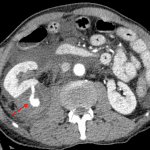

- Obscuring of the right psoas shadow

- Retroperitoneal hematoma

Obscuring of the right psoas shadow, which raises concern for an adjacent mass or hematoma. Recommend CT for further evaluation.